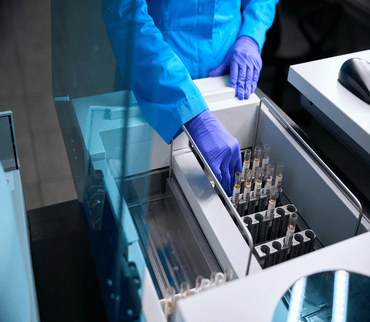

External Quality Assurance (EQA) is essential for ensuring the accuracy, reliability, and comparability of laboratory test results. It helps laboratories identify errors, monitor performance over time, and maintain compliance with national and international standards. By participating in EQA, laboratories build confidence among clinicians and patients, ultimately improving patient care and supporting better clinical decision-making.

Our Proficiency Testing Schemes

Our Proficiency Testing Schemes

The robust external quality assurance for medical laboratories